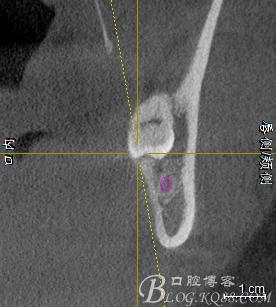

口內(nèi):38未萌出。37遠(yuǎn)中牙周袋10mm,CT:38牙冠倒置。牙齦紅腫,捫診可有少量血性滲出,無(wú)波動(dòng)感。印象診斷:38冠周炎。處理:1.抗炎治療,改善張口度。2.炎癥消退后,拔除38.

一、術(shù)前CBCT影像資料